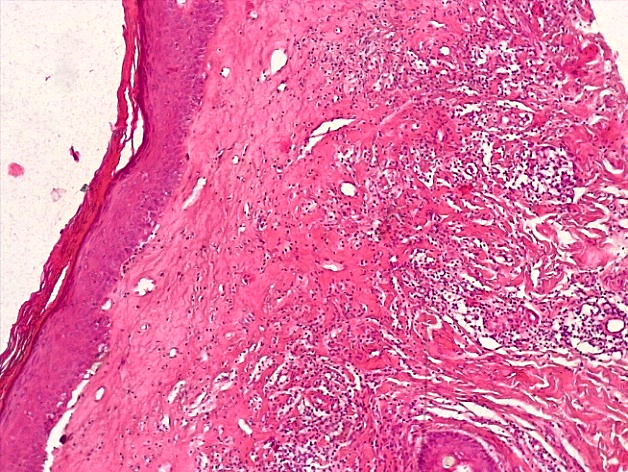

При морфологическом исследовании биоптатов вульвы пациенток с атрофическим вариантом течения СЛВ наибольшие изменения наблюдались со стороны эпидермиса и поверхностных слоев дермы. В эпидермисе отмечалась резкая атрофия клеток многослойного плоского эпителия (МПЭ) с участками повышенного ороговения (гиперкератоза и паракератоза), в некоторых случаях были выявлены участки фибриноидного некроза с окружающей лейкоцитарной клеточной инфильтрацией (рис. 1), указывающие на наличие очагов острого язвенного повреждения эпидермиса на фоне дистрофических и регрессивных изменений многослойного плоского эпителия. При этом количество клеточных слоев эпидермиса было уменьшено в среднем до 3–4 с избыточным образованием роговых чешуек в поверхностных слоях, а количество базальных клеток эпидермиса в 1 мкм не превышало 10, что свидетельствовало об атрофии резервного слоя эпидермиса (рис. 2).

Рис. 2. Атрофический вариант течения СЛ вульвы. Неравномерная атрофия и хроническое воспаление кожи с развитием фиброзной ткани (окраска гематоксилином-эозином, х100)

Fig. 2. Atrophic variant of the course of the vulva SL. Uneven atrophy and chronic inflammation of the skin with the development of fibrous tissue ((hematoxylin-eosin staining, x 100)